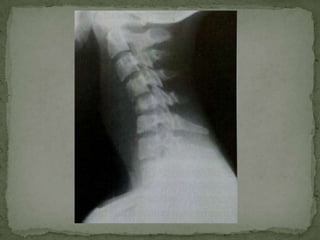

Anterior Subperiosteal –

 begins at the anterior vertebral margin underneath the

periosteum

 spreads beneath the ALL

 subtle anterior erosions of multiple vertebrae

 clinical symptoms are severe in relation to the minor

radiographic abnormalities

 Disk destruction maybe late and anterior erosions are

difficult to detect on plain radiographs.

Anterior sub-periosteal